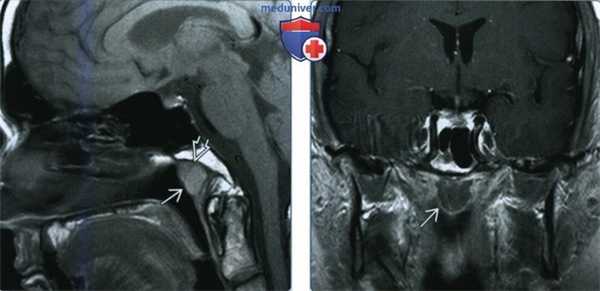

(Слева) При МРТ Т1ВИ в сагиттальной проекции у пациента с кистой Торнвальда средних размеров В определяется несколько повышенная интенсивность сигнала, вероятно, за счет повышенного содержания белка. Внутри кисты имеются небольшие перемычки.

(Справа) При МРТ FS с КУ в коронарной проекции (срез через гипофиз) определяется киста Торнвальда, которая не накапливает контрастное вещество. В слизистой оболочке носоглотки контраст накапливается.